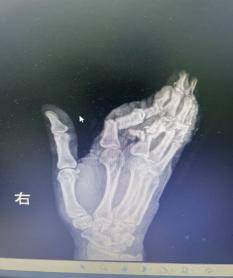

1小時前,余女士還在工作,一個不留神,粉碎機(jī)擠壓到了她的手,右手瞬間卷入機(jī)器。劇烈的疼痛襲來,當(dāng)她抽出手時,眼前的一幕讓她幾乎暈厥——食指、中指、無名指已完全離斷,只有少許皮膚還連著,小拇指也血肉模糊。

抵達(dá)醫(yī)院時,航醫(yī)骨外科值班醫(yī)生已接到通知,在急診待命。接到余女士的那一刻,值班醫(yī)生迅速上前為她查看傷情“您別擔(dān)心,一切有我們”,經(jīng)快速檢查,診斷明確:余女士的右手多指完全離斷傷。這是一類極為嚴(yán)重的手部創(chuàng)傷,斷指再植手術(shù)的黃金時間僅有6-8小時,一旦治療時間稍有延誤,難以保證手指存活。

手術(shù)的難度超乎想象:

血管細(xì)如發(fā)絲:手指的動靜脈直徑僅0.3-0.8毫米,醫(yī)生需要在顯微鏡下用比頭發(fā)絲還細(xì)的縫線進(jìn)行吻合;

多指同時再植:余女士食指、中指、無名指三指離斷,需同時重建血運(yùn),給手術(shù)醫(yī)師的精力和體力帶來極大考驗(yàn);

小拇指皮瓣修復(fù):小拇指軟組織缺損嚴(yán)重,醫(yī)生將精心設(shè)計(jì)皮瓣覆蓋創(chuàng)面,避免術(shù)后壞死;

骨折內(nèi)固定+肌腱神經(jīng)修復(fù):不僅要讓手指“活”,更要讓手指“能用”。